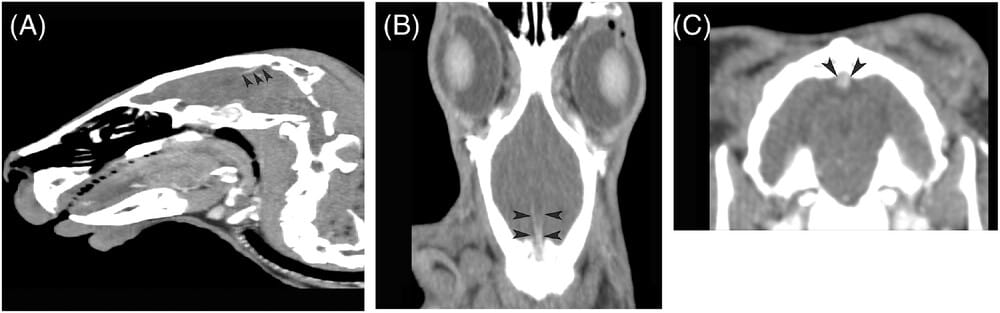

Postcontrast CT of a 3-year-old female spayed Holland Lop (0.63 mm slice thickness, pitch 0.938, helical scan, kvp 120, matrix 512 × 512). Mild contrast enhancement within the confluence sinuum and straight sagittal sinus on sagittal (A), dorsal (B), and transverse (C) planes (black arrowheads). Mild contrast enhancement was defined as a thin linear region of contrast-enhanced tissue within the region of the confluence sinuum that extended rostroventrally to the straight sinus bilaterally.

Results: Contrast enhancement was identified in all rabbits (24/24) on contrast-enhanced CT imaging. Contrast enhancement was mild in 45.8% (11/24) rabbits, moderate in 33.3% (8/24), and marked in 20.8% (5/24). There were significant differences (P < 0.05) between the average HU of the mild and marked group and the moderate and marked groups. Two rabbits with marked contrast enhancement were initially misdiagnosed with an intracranial, extra-axial mass based on contrast-enhanced CT, but necropsy confirmed normal brain parenchyma.

Conclusions: The study described the variable features of the normal confluence sinuum and straight sinus in rabbits on contrast-enhanced CT. The confluence sinuum can be variable in size and shape and should not be mistaken for a pathological lesion in the absence of mass effect or secondary calvarial changes. Recognition of the normal lagomorph cerebral venous system and its variation in size is clinically important to prevent misdiagnoses.